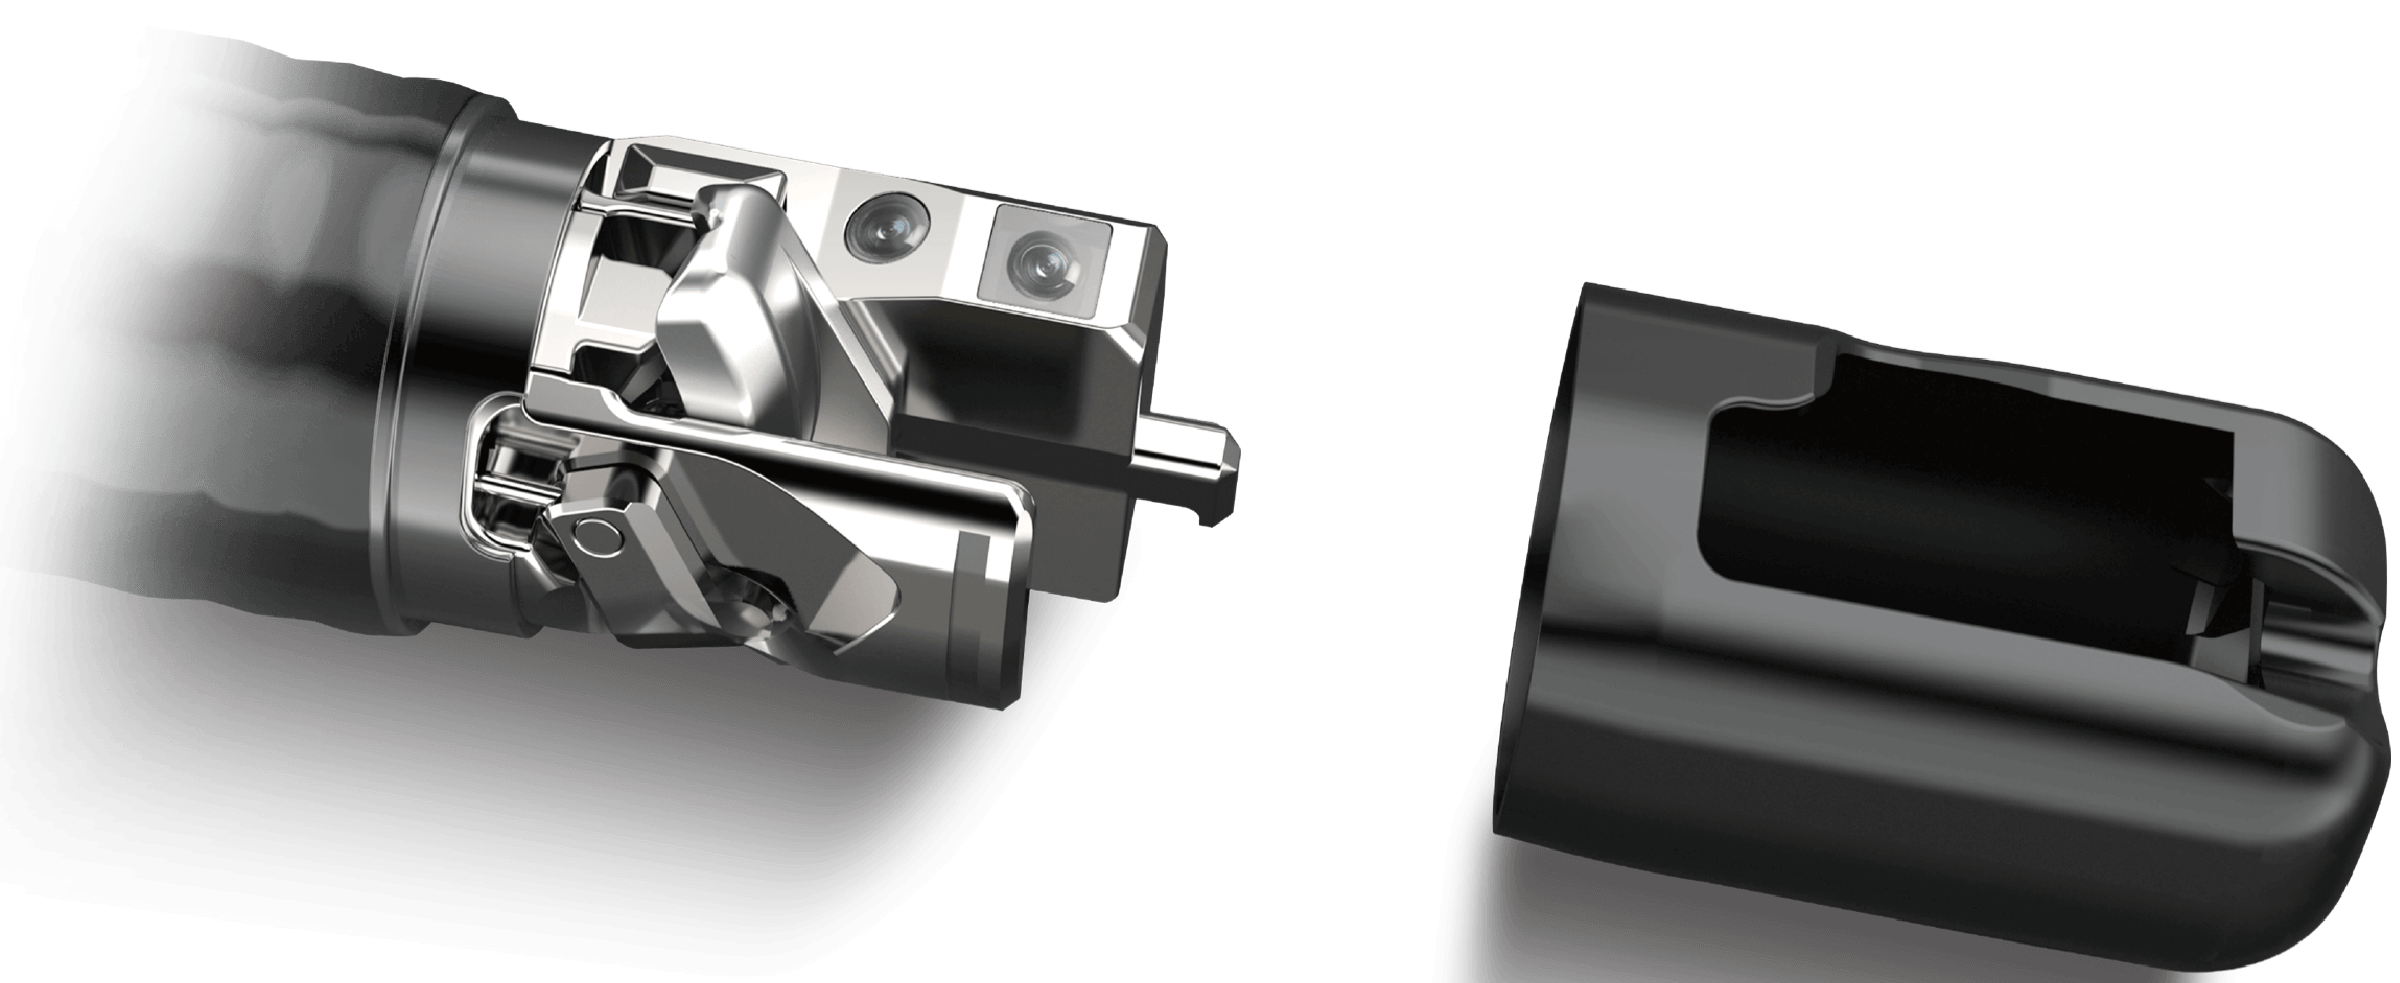

可拆卸先端帽

提供独立抬钳器清洗装置

4.2mm大钳道,器械交换更顺畅